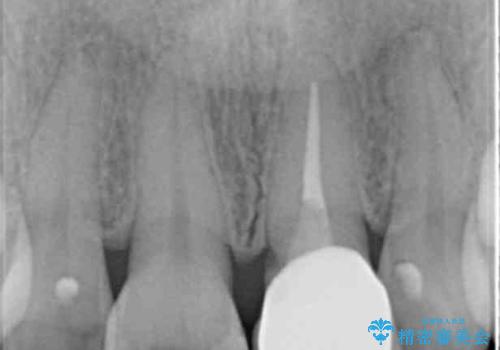

- 10年以上前に神経を取り除いた前歯の変色が気になるとのことで来院された患者様です。

レントゲン写真より、歯根の炎症が認められなかったため、ファイバーコアによる土台築製後、オールセラミッククラウンにて補綴することとしました。